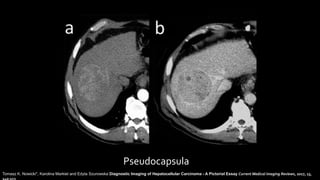

Pseudocapsula

Tomasz K. Nowicki*, Karolina Markiet and Edyta Szurowska Diagnostic Imaging of Hepatocellular Carcinoma - A Pictorial Essay Current Medical Imaging Reviews, 2017, 13,

20% son hipovasculares